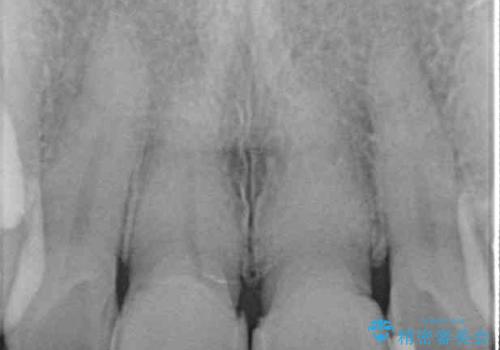

- つぎはぎのある前歯のセラミックの色合いが気になるとのことで来院された患者様です。

グレーの色が透けて見える気がする点が気になっていらっしゃり、やや黄色みのある色を希望されていました。

仮歯に置き換えた後にオールセラミッククラウンにて補綴治療を行うこととしました。